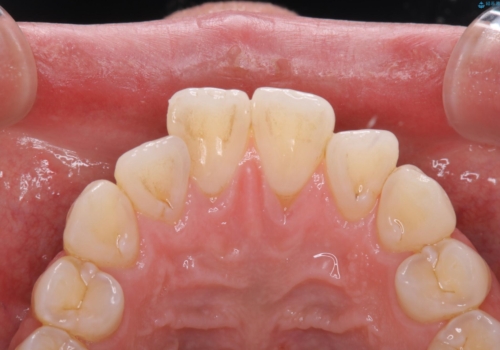

PMTCを初めてやったとのことで、全体的にステイン、プラーク、歯石が多く付着していました。これから虫歯の治療や矯正がスタートするため、歯茎が腫れていたり、汚れが付着していると、虫歯や歯周病が進行してしまうため、治療と並行してブラッシング指導、クリーニングを行っています。何よりも日々のクリーニング(ホームケア)が大切なため、頑張っています。